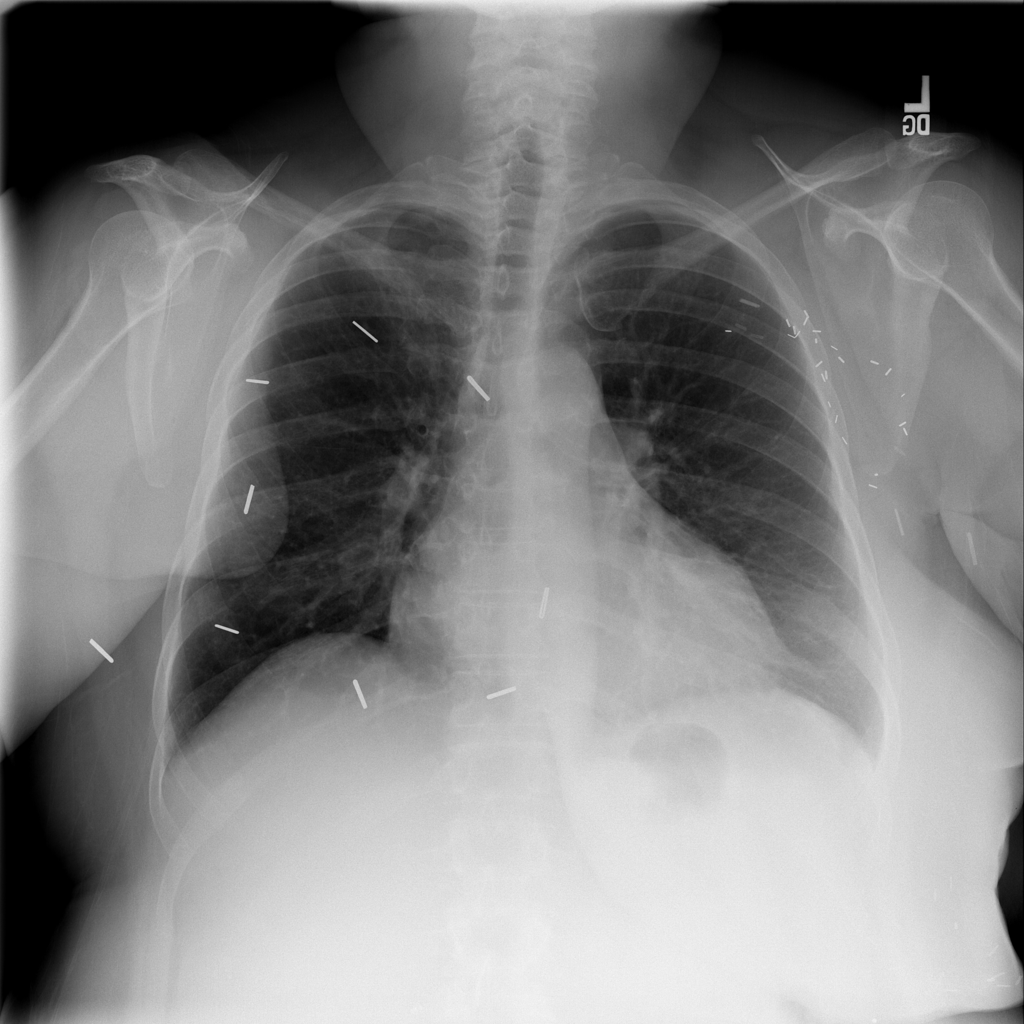

PAT-4639 · IMG-045Cardiomegaly

PAT-4639 · IMG-045

PA